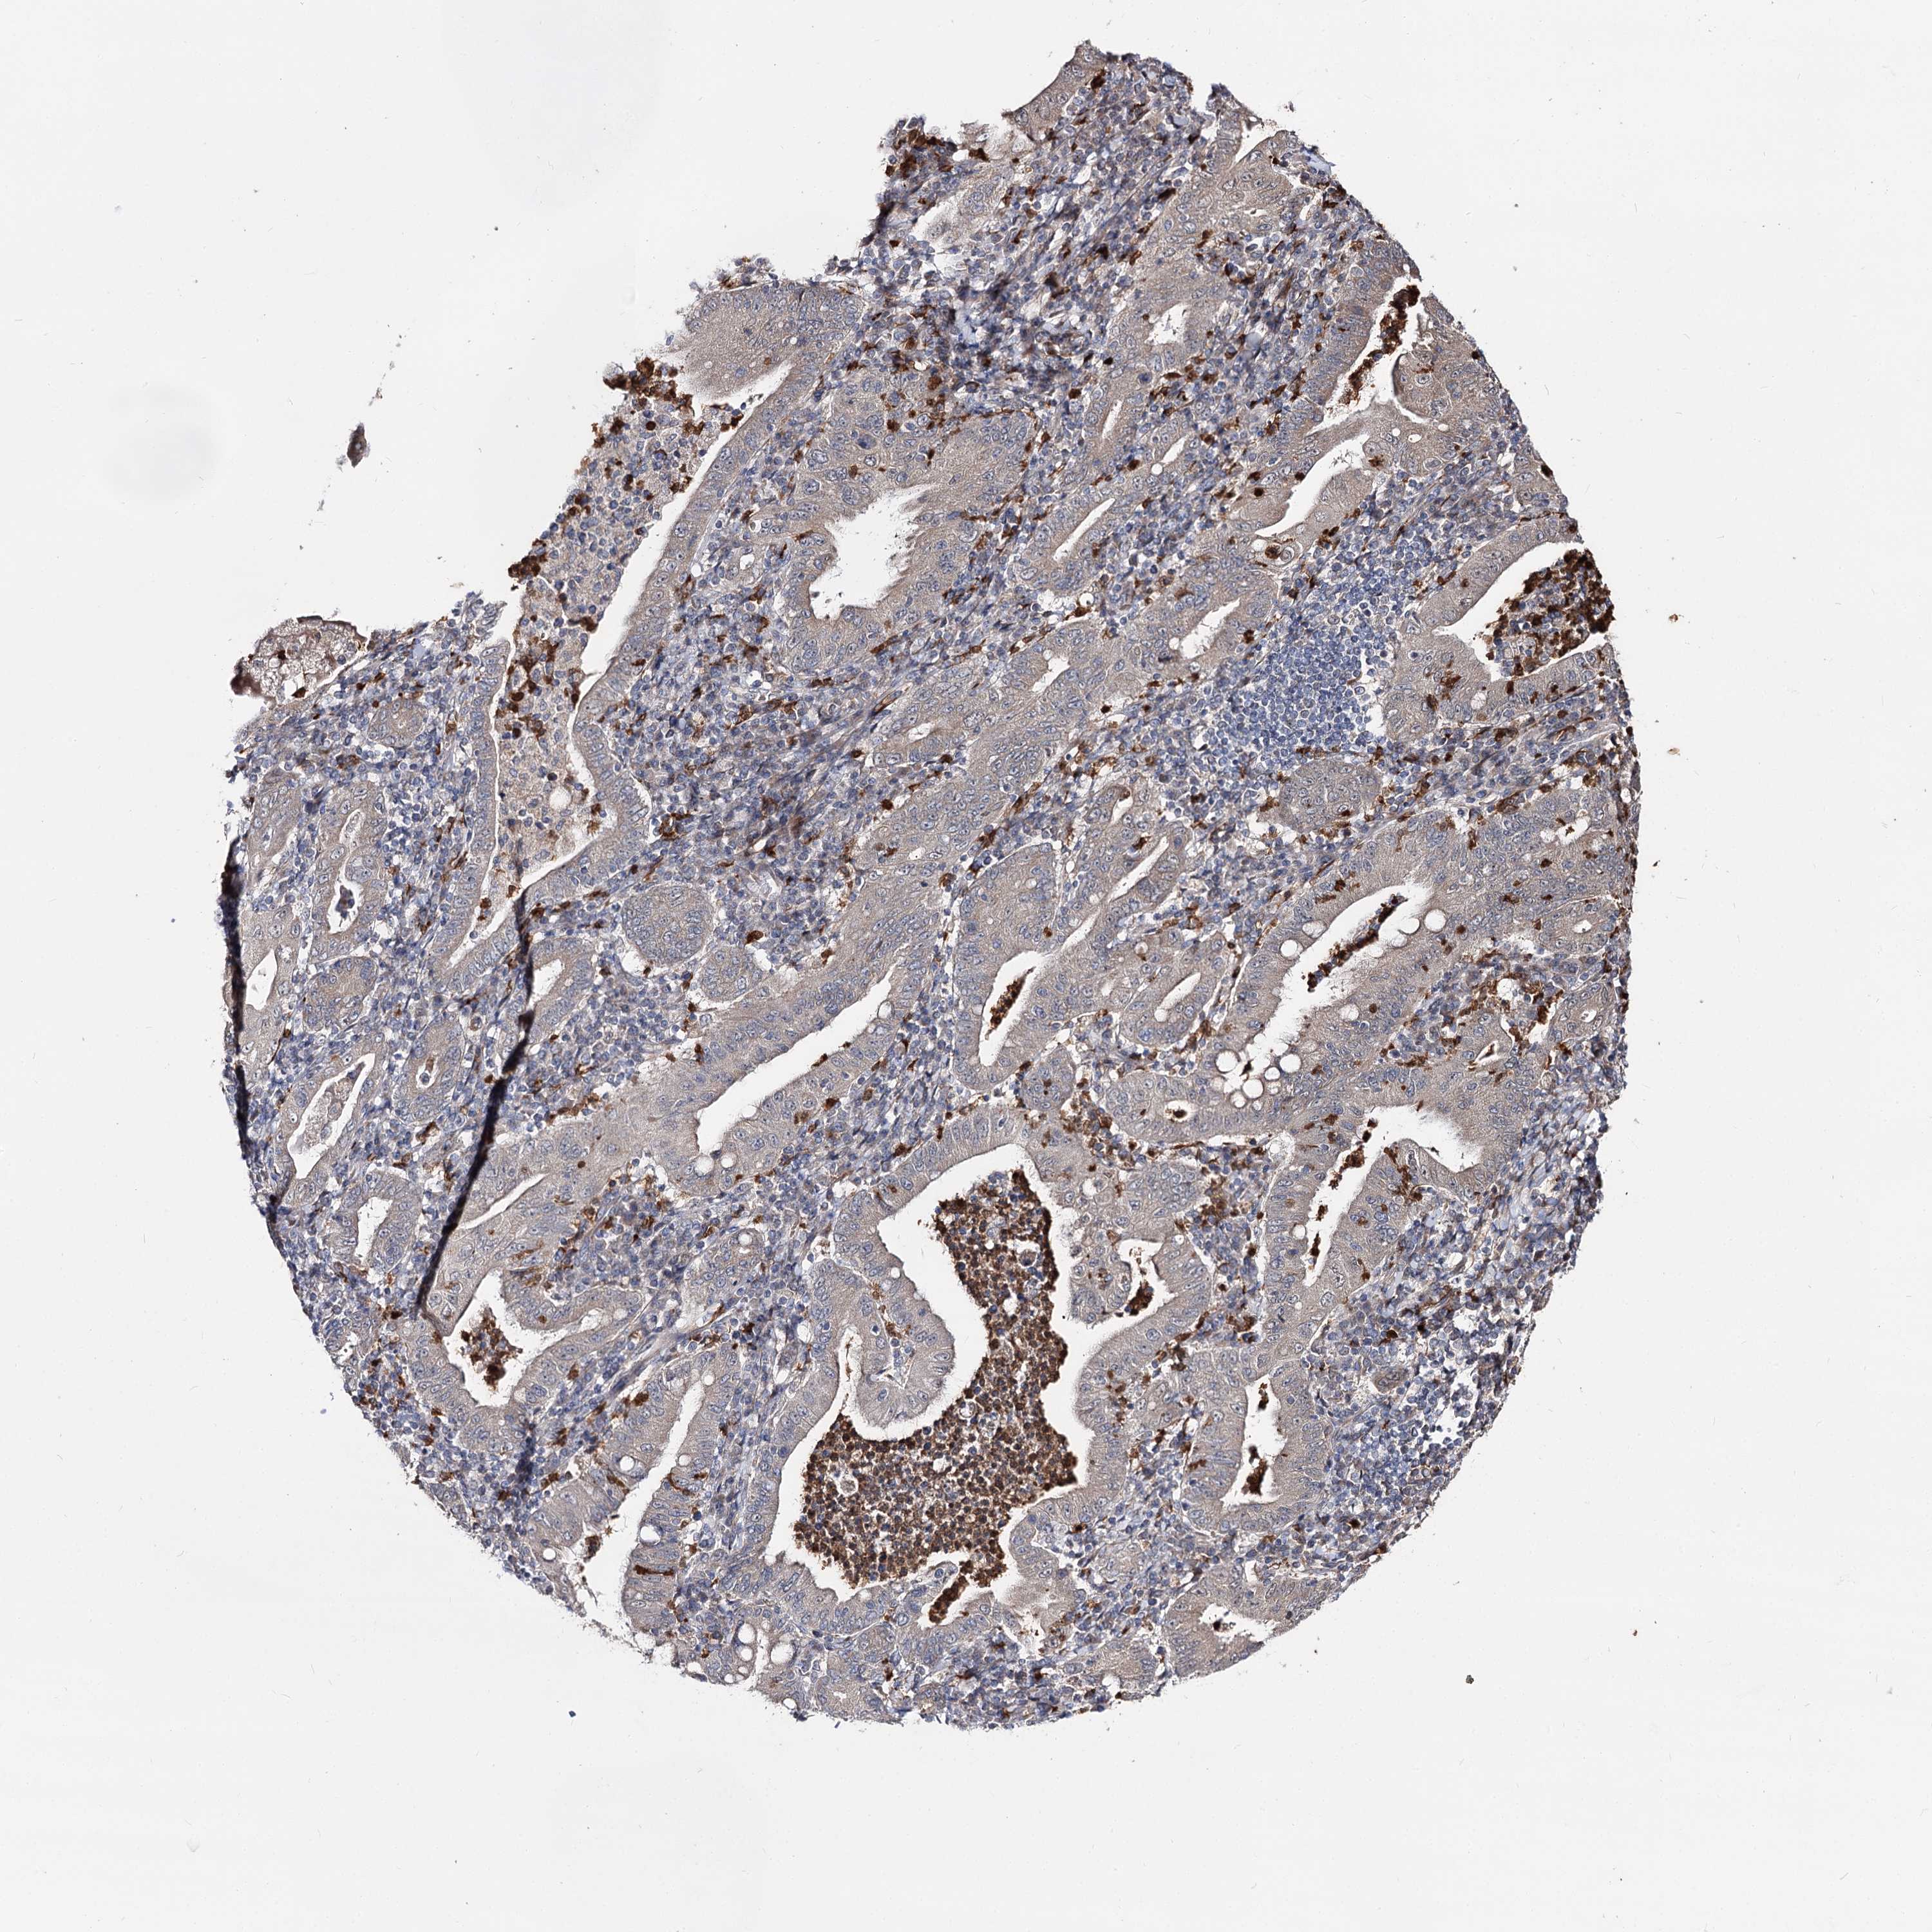

STOMACH CANCER - Protein expressioni

A mouse-over function shows sample information and annotation data. Click on an image to view it in a full screen mode. Samples can be filtered based on level of antibody staining by selecting one or several of the following categories: high, medium, low and not detected. The assay and annotation is described here.

Note that samples used for immunohistochemistry by the Human Protein Atlas do not correspond to samples in the TCGA dataset.

Antibody stainingi

Antibody staining in the annotated cell types in the current human tissue is reported as not detected, low, medium, or high, based on conventional immunohistochemistry profiling in selected tissues. This score is based on the combination of the staining intensity and fraction of stained cells.

Each image is clickable and will lead to virtual microscopy that enables deeper exploration of all samples and also displays staining intensity scores, fraction scores and subcellular localization as well as patient and tissue information for each sample.

Antibody HPA038040

Staining

High

Medium

Low

Not detected

Intensity

Strong

Moderate

Weak

Negative

Quantity

>75%

75%-25%

<25%

None

Location

Nuclear

Cytoplasmic/membranous

Cytoplasmic/membranous,nuclear

Adenocarcinoma, NOS

Adenocarcinoma, High grade